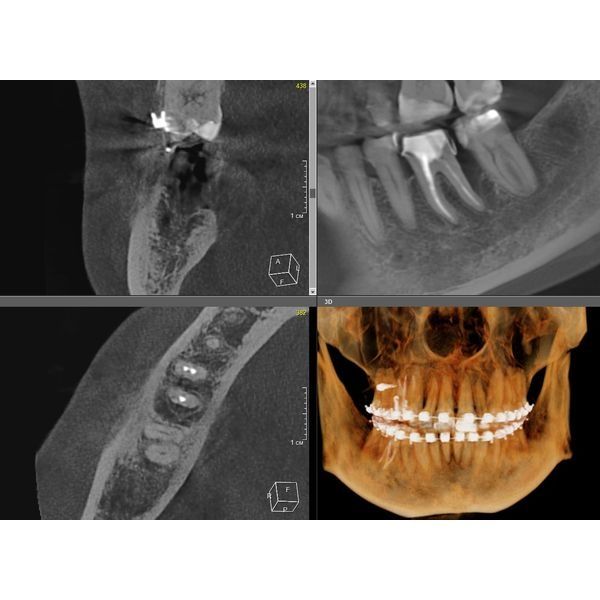

Провели компьютерную томографию — КЛКТ, т. е. 3D-рентген обеих челюстей: выявили неравномерную деструкцию костной ткани в области жевательной группы зубов нижней челюсти до 2/3 длины корня зуба, в области остальных зубов — до 1/3 длины корня.

На пародонтограмме (графическом изображении всех зубов с каждой стороны) визуализировались глубокие пародонтальные карманы в области жевательных зубов нижней челюсти и множественные пародонтальные карманы в области всех зубов верхней челюсти.